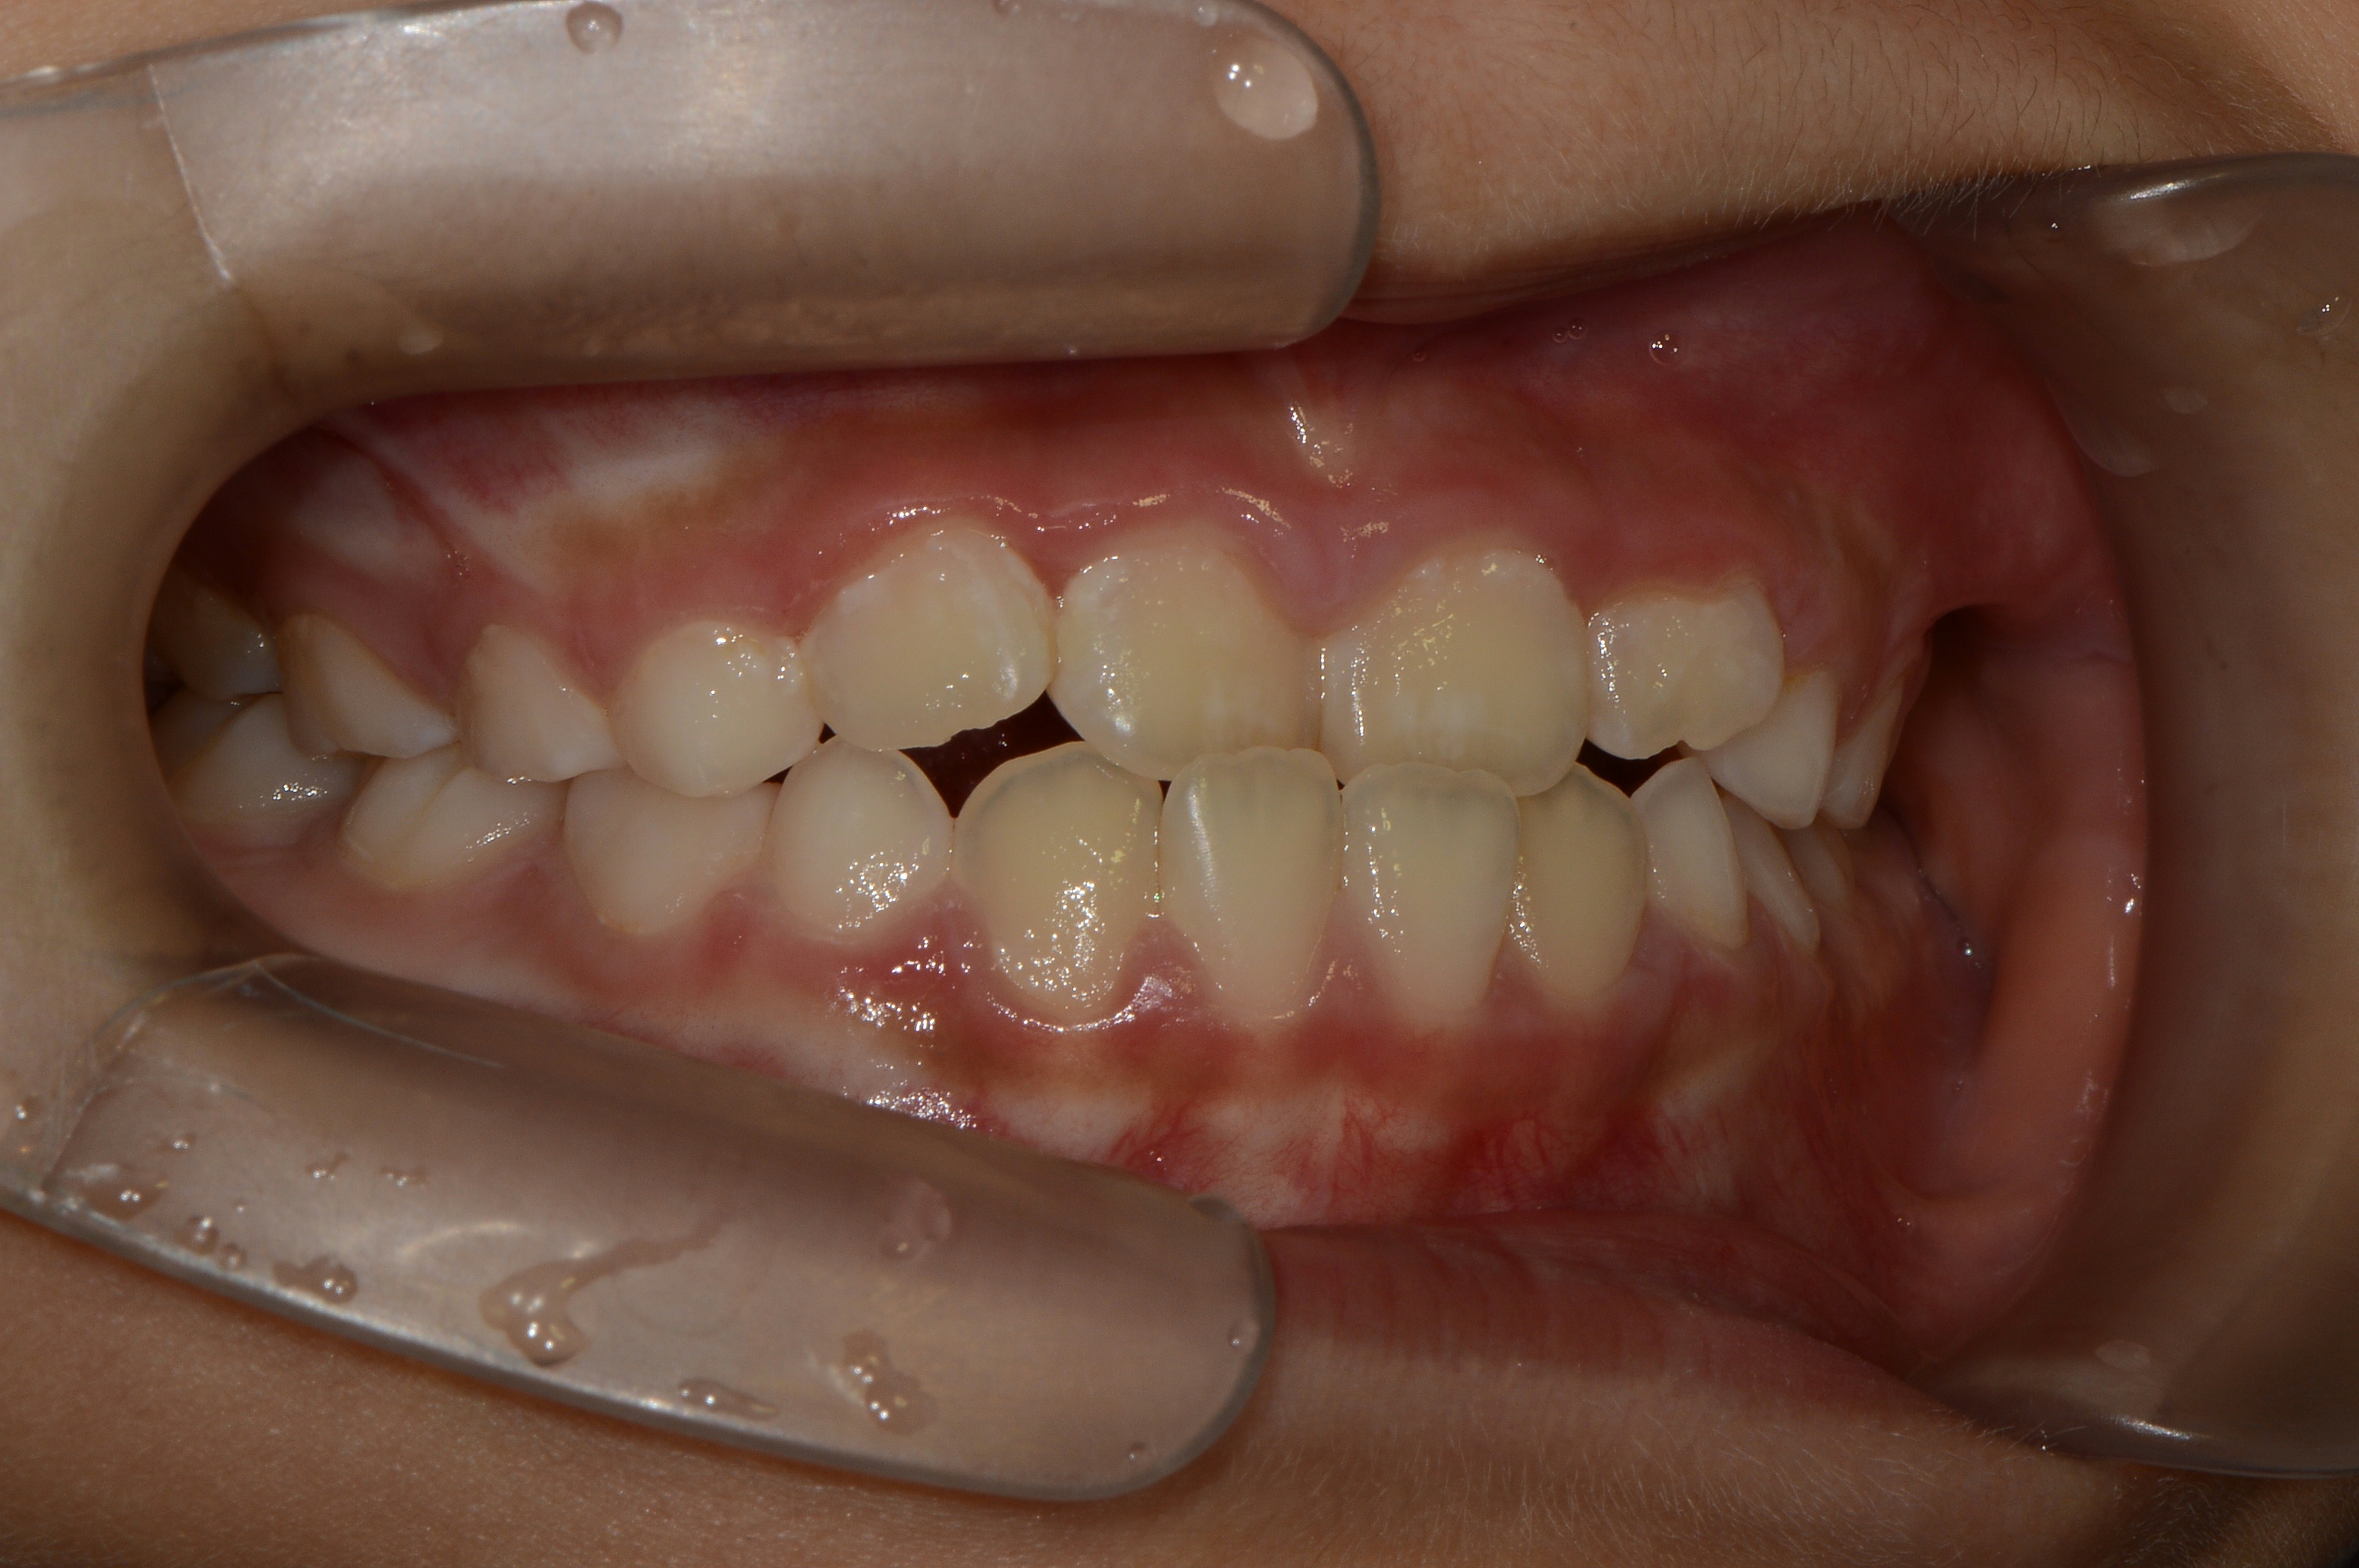

치료 전 사진입니다.